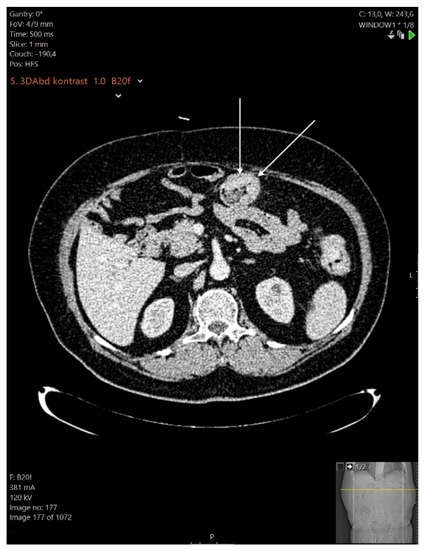

Case Report

A Rare Case of Multiple Gastrointestinal Stromal Tumors Coexisting with a Rectal Adenocarcinoma in a Patient with Attenuated Familial Adenomatous Polyposis Syndrome and a Mini Review of the Literature

by Daniel Paramythiotis, Filippos Kyriakidis, Eleni Karlafti, Triantafyllia Koletsa, Anastasia Tsakona, Petros Papalexis, Aristeidis Ioannidis, Petra Malliou, Smaro Netta and Antonios Michalopoulos

Medicina 2022, 58(8), 1116; https://doi.org/10.3390/medicina58081116 - 18 Aug 2022

Abstract

Background: Multiple gastrointestinal stromal tumors (GISTs) are extremely rare entities that exist either as spontaneous GISTs or as part of various syndromes, such as Carney’s triad and type I neurofibromatosis (NF1). Attenuated familial adenomatous polyposis (AFAP) is a variant of familial adenomatous polyposis [...] Read more.

Background: Multiple gastrointestinal stromal tumors (GISTs) are extremely rare entities that exist either as spontaneous GISTs or as part of various syndromes, such as Carney’s triad and type I neurofibromatosis (NF1). Attenuated familial adenomatous polyposis (AFAP) is a variant of familial adenomatous polyposis (FAP) with a milder clinical presentation. Both GISTs and AFAP have been reported to coexist with colorectal cancer, but the coexistence of GISTs and AFAP has never been reported in the literature before. Case report: A 45-year-old male patient with known AFAP arrived scheduled for a total colectomy and ileo-rectal anastomosis due to the malignancy of one of the previously biopsied polyps of the upper rectum. Intraoperatively, multiple nodular tumors were found at the jejunum within a length of 45 cm, for which an enterectomy and enteroanastomosis were performed. A histopathological examination of the whole colectomy specimen confirmed the presence of multiple polyps in the large intestine along with a rectal invasive adenocarcinoma. At the same time, in the examined part of the small intestine, 15 GISTs sized from 0.5 to 2.0 cm of prognostic group I, were identified. The patient’s postoperative course was uncomplicated. Conclusion: Multiple GISTs may present as an asymptomatic disease, and the same thing is true for colorectal cancer. Therefore, the appropriate screening is crucial for entities such as AFAP, since the surgery was performed because of the malignant transformation in one of the polyps and revealed multiple GISTs, as well. Full article